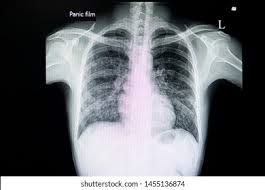

Interstitial lung disease radiology. On a Chest X-Ray it can be very difficult to determine whether there is interstitial lung disease and what kind of. Leflunomide-induced acute interstitial pneumonia. IIPs include seven entities.

Interstitial lung disease results in six distinct radiologic patterns of abnormality. Interstitial lung disease ILD drug-induced interstitial lung disease. We describe demographic radiologic histopathologic and molecular features and p16 expression in patients with telomeres 10th percentile shortened telomeres and compare them to patients with telomere length 10th percentile.